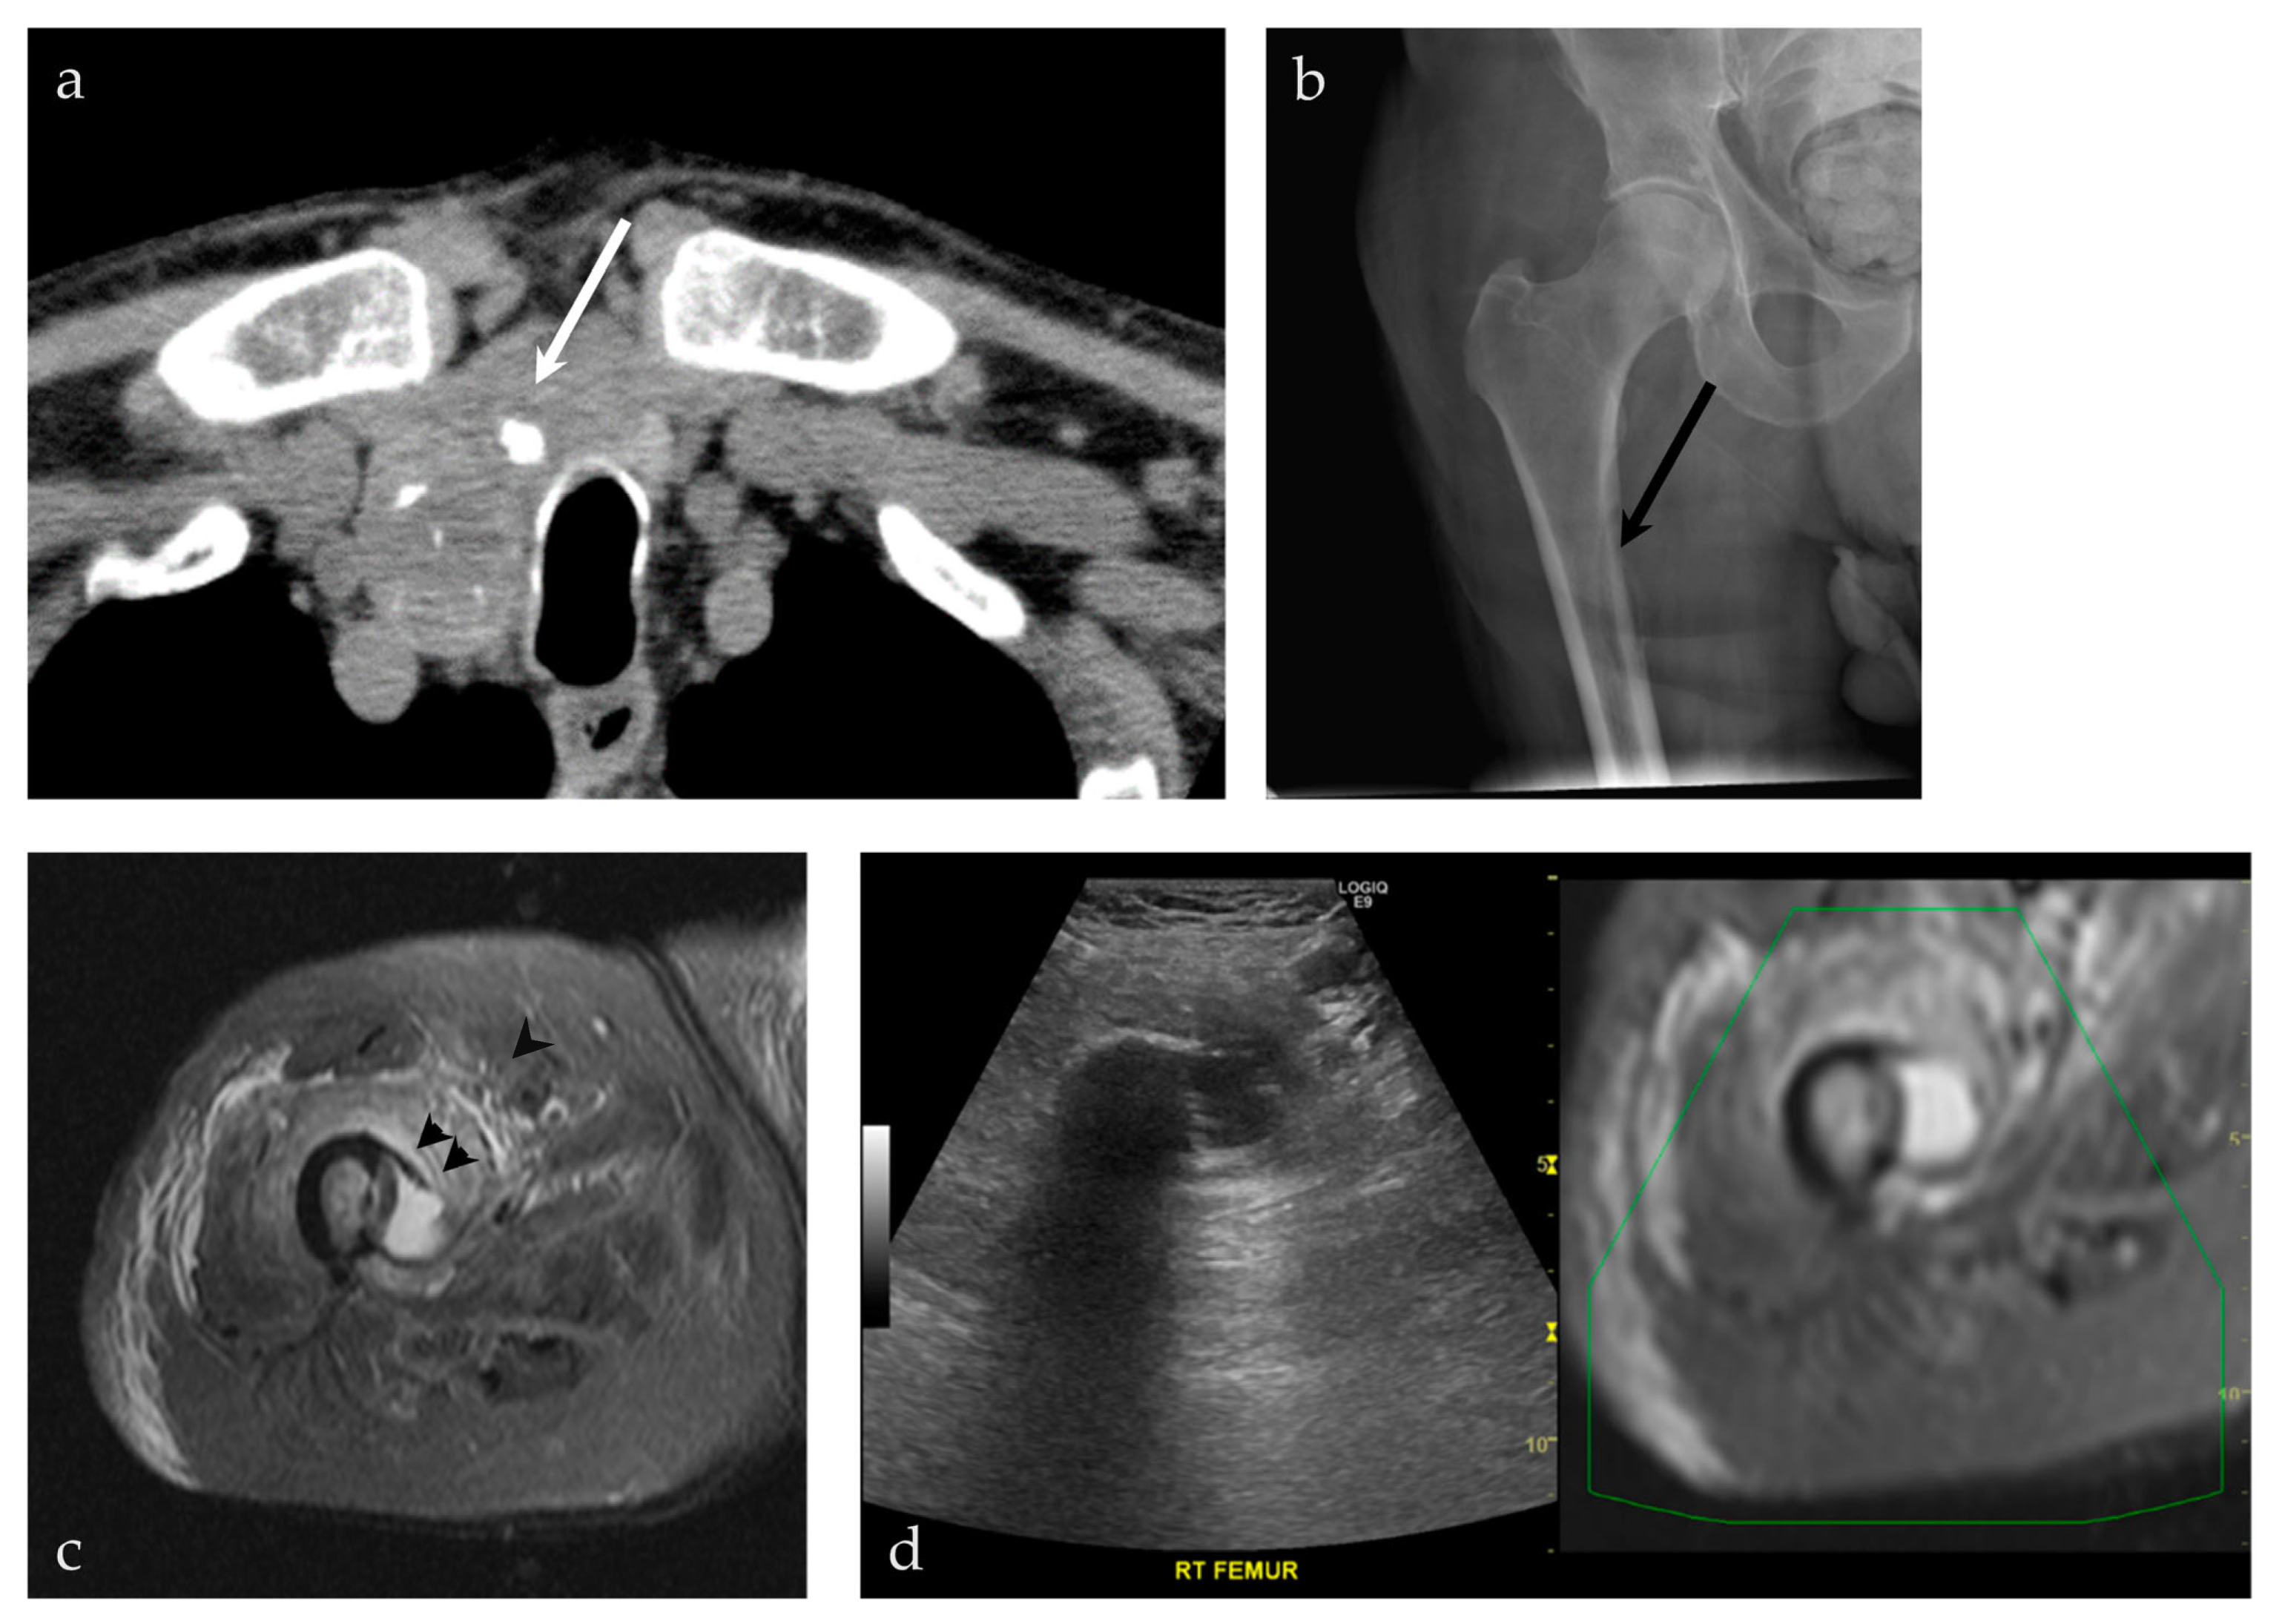

3.2.4. Targeted Percutaneous Lesion Biopsy and/or Aspiration

| 45/M | Right acromion | US-MRI | Epithelioid hemangioma | Neoplastic, benign |

| 93/M | Right femur | US-MRI | Metastatic disease, papillary thyroid carcinoma | Neoplastic, malignant |

| 53/M | Right thigh | US-CT | Necrotic muscle | ???? *** |